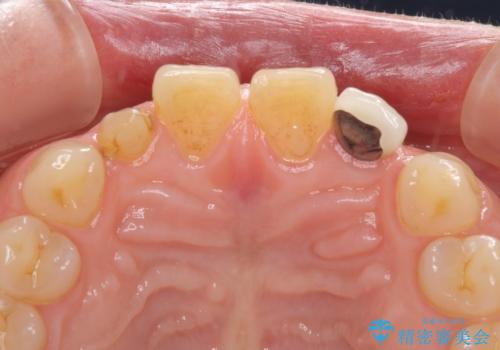

- 前歯の矮小歯に貼り付けられていたラミネートベニアが外れてしまったとのことで来院された患者様です。

反対側の矮小歯は裏打ちが金属であったため、両方の歯ともにオールセラミッククラウンにて補綴することとしました。